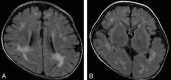

Fig 1.

Type 1. Nonspecific brain atrophy. T1WI (A) and T2WI (B) of a 9-year-old patient (case 4) with an ATRX mutation of the ADD domain in exon 6 (c.390_391 ins A; E131fs). Nonprogressive diffuse cortical brain atrophy and ventricular enlargement due to loss of white matter volume are shown.